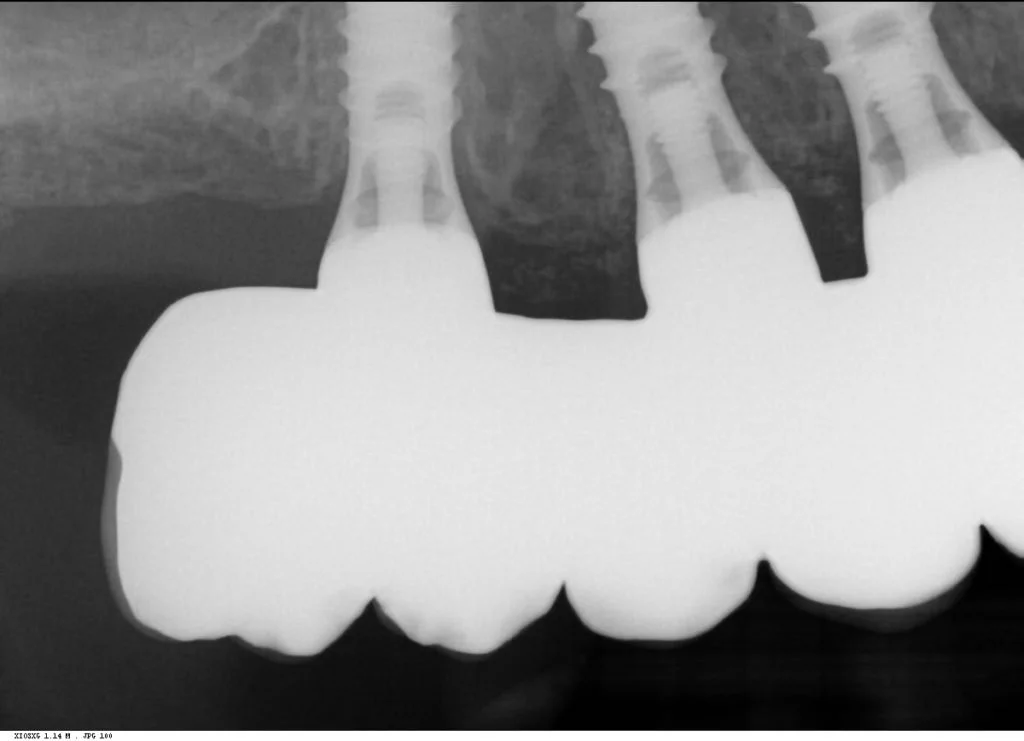

Multiple intra-operative radiographs were taken using depth gauges of gradually increasing diameter to ensure ideal positioning, particularly near vital structures such as the maxillary sinus. Following three months healing, definitive impressions were taken. Radiographs were taken to confirm complete seating of the impression copings prior to splinting of the impression copings and then impression taking.

Records stage: due to the fact that all records were gained by the adjustment and confirmation of the provisional removable complete maxillary denture, records were quite straightforward. The complete denture was copied, flanges were removed, and the resulting guide was then seated over the existing tissue level healing abutments. A PMMA bridge with plastic inserts was constructed digitally in the laboratory and sent for final confirmation prior to construction of the definitive porcelain-fused-to-zirconia bridge. The definitive bridge was inserted and radiographs were taken to confirm full seating and correct emergence profile. Once passivity of fit was confirmed, abutments crews were torque to 35 Ncm, and the access cavities were restored with PTFe tape and composite resin. The occlusion was adjusted to ensure guiding services were smooth, concave and gradually increasing pre-truce in steepness, and smooth shared group function in lateral excursion.